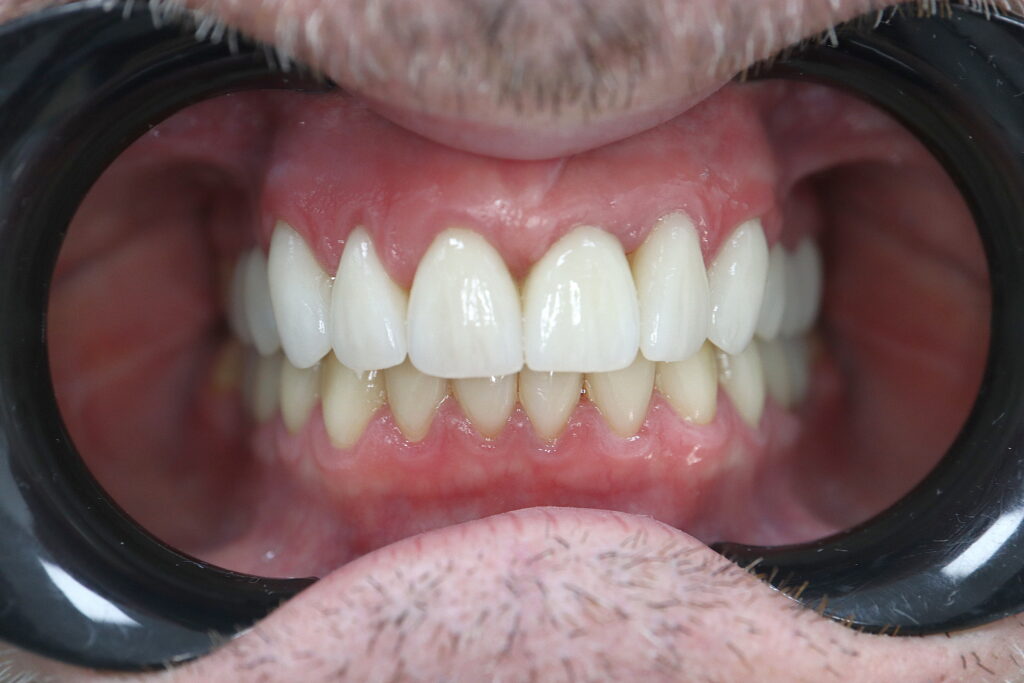

Результаты ортопедического этапа

Стоимость протезирования: 8800 USD (цена указана ориентировочно по курсу НБРБ на день оплаты)

Протезирование выполнено врачом-ортопедом Агаевым Самиром Вахидовичем.

результат протезирования